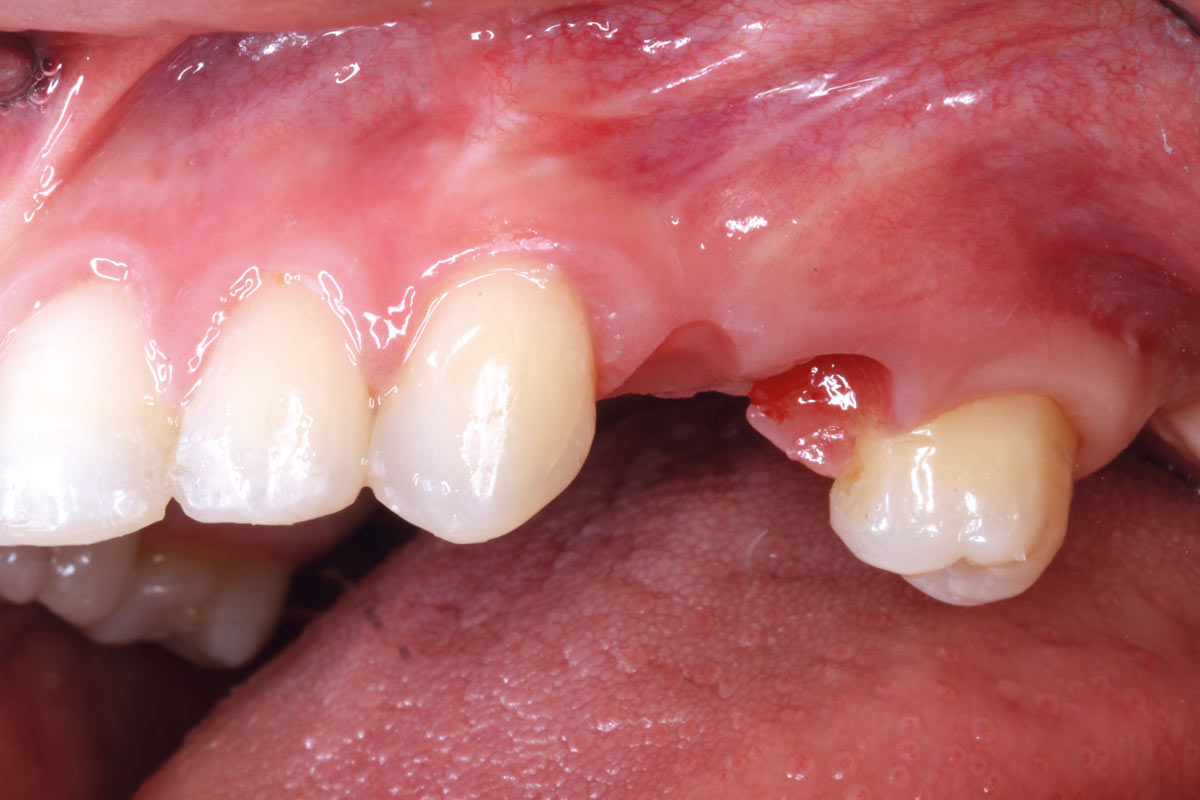

Intact socket following atraumatic tooth extraction